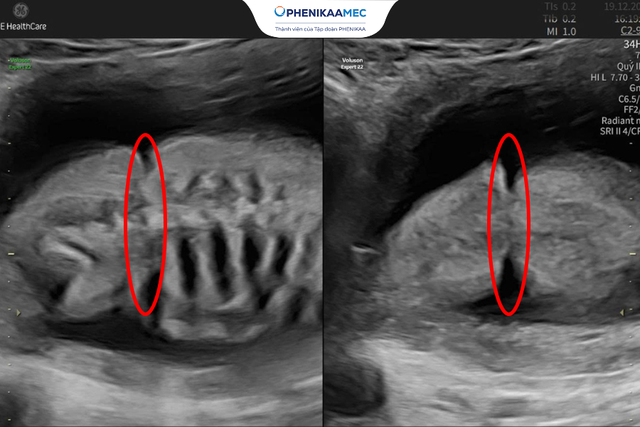

Hình ảnh dải xơ buồng ối thắt ngang lưng em bé trên hình ảnh siêu âm

Trong trường hợp thai nhi dải xơ buồng ối, thay vì lựa chọn can thiệp - vốn tiềm ẩn nhiều rủi ro - TS. BS Sim chọn theo dõi chặt chẽ. Quyết định đó giúp thai kỳ tiếp tục an toàn, và em bé sau đó chào đời khỏe mạnh.